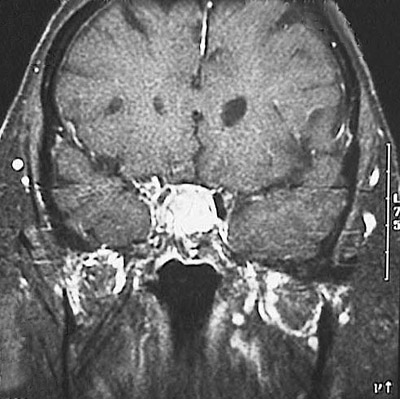

This coronal view MRI scan of the head reveals a pituitary adenoma filling and expanding the sella turcica.